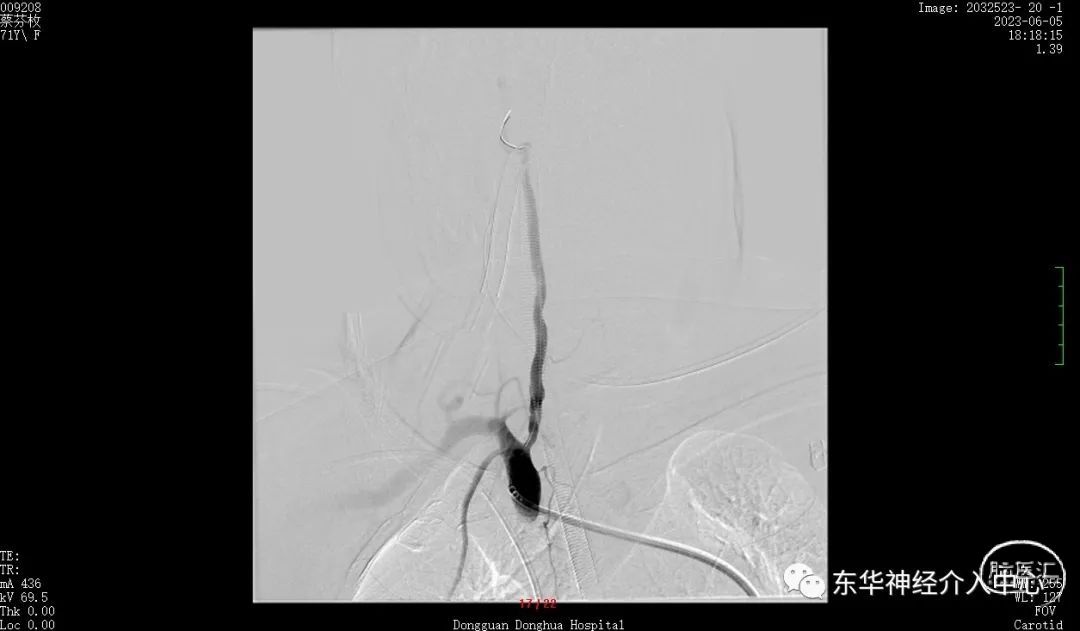

如此信心大增。继续填塞。终于满意的将动脉瘤栓塞,动脉瘤完全不显影。

术后3D DSA动态显示栓塞满意、PICA血流无任何影响。